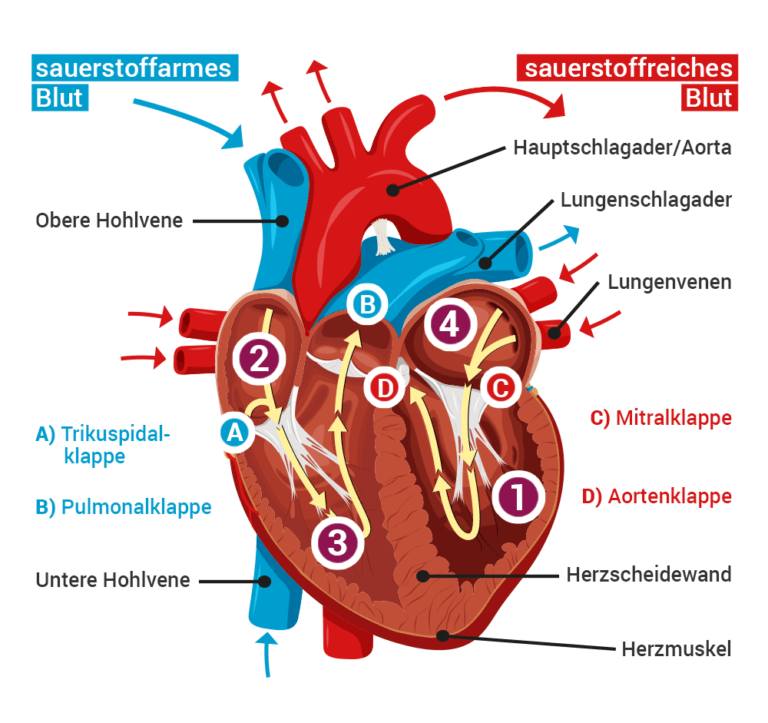

Die Pumpleistung ist die Menge des Blutes, die das Herz innerhalb einer bestimmten Zeit in den Blutkreislauf pumpt. Das gesunde Herz eines erwachsenen Menschen pumpt in Ruhe etwa 5 bis 6 Liter pro Minute. Bei einer körperlichen Belastung steigt dieses Herzminutenvolumen auf 20 bis 25 Liter. Krankheiten können die Pumpleistung des Herzens unnatürlich senken oder steigern.. In jeder Minute wird so einmal die gesamte Blutmenge – beim Erwachsenen fünf bis sechs Liter – durch den Körper befördert. Doch wie schafft das Herz jeden Tag diese Schwerstarbeit und wie funktioniert diese menschliche Pumpe? Herz-Kreislauf-System: So fließt das Blut. Das Herz ist das Zentrum des Blutkreislaufs.

Das Herzzeitvolumen (HZV, englisch cardiac output CO) ist das Volumen des Blutes, das pro Zeitspanne vom Herzen gepumpt wird (Volumenstrom).Die übliche Maßeinheit in der Humanmedizin ist Liter pro Minute, wobei dann vom Herzminutenvolumen (HMV), früher auch Minutenvolumen des Herzens, gesprochen wird.. Das Herzzeitvolumen ist ein Maß für die Pumpleistung des Herzens bezüglich der.. Der venöse Rückstrom zum Herzen bestimmt ganz wesentlich, wie viel Blut das Herz jede Minute auswirft. Abhängig von diesem Rückfluss pumpt das Herz automatisch das zurückströmende Blut in den Körperkreislauf. Je mehr Blut zurückströmt, desto mehr Blut wird vom Herzen ausgeworfen und umgekehrt.